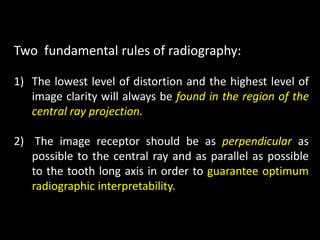

2. The paralleling cone technique provides accurate images with little magnification and no superimposition but is more difficult for patients. The bisecting angle technique is easier for patients but results in more image distortion.